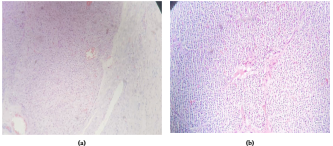

病理检查显示巨大的卵巢组织,有两个肉眼可见的黄色瘤样颗粒囊肿,大小分别为1.5cm×1cm和1cm×1cm。在组织学上,两个细胞团中都有颗粒状黄体化细胞,但其余为正常卵巢组织,伴有出血和两个滤泡囊肿,有2-3个核分裂/10 HPF(图3a-b)。最后诊断为妊娠黄体瘤,无明显恶性。

图3.(a,b)显微镜观察HE染色后卵巢组织